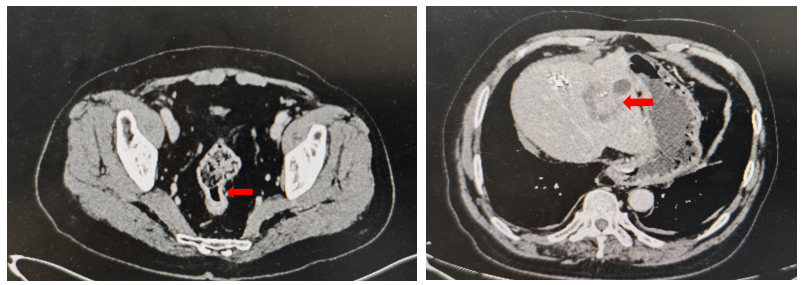

CT检查提示乙状结肠壁增厚,伴肝脏多发转移(图1)。

乙状结肠癌伴多发肝转移。